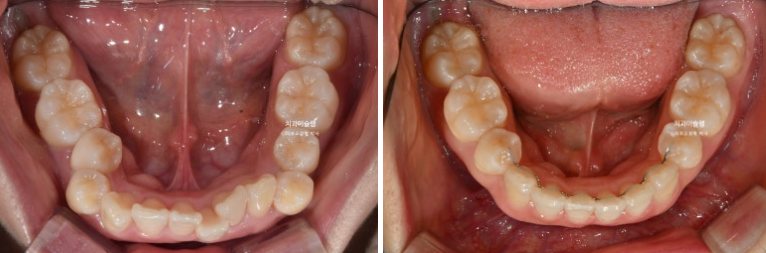

이제 전후 비교 보겠습니다.

총 치료기간은 3년 2개월, 재제작은 3회 했습니다.

2022.11~2026.01

아래 앞니는 계획대로 뒤로 1mm도 뒤로 들어감 없이 잘 유지가 되었고 위 앞니는 치조골이 허용하는 범위 내에서 아래앞니와 만나기 위해 최대한 뒤로 들어갔습니다.